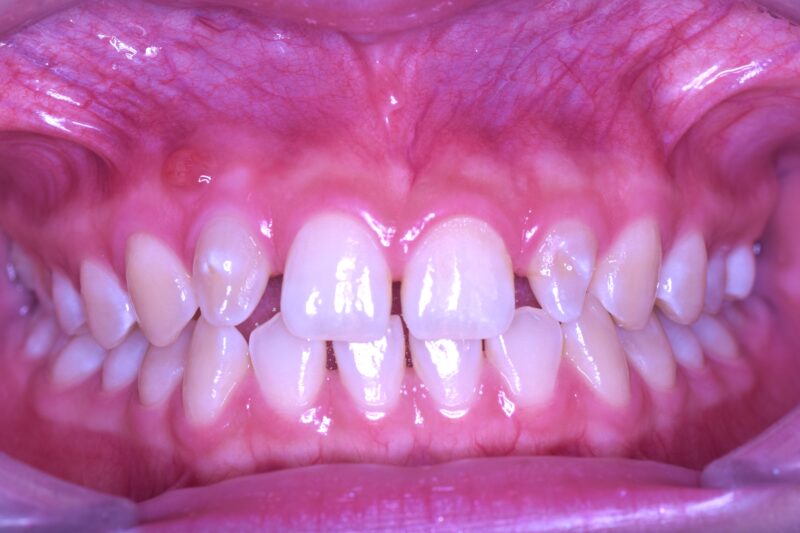

【初診時口腔内写真】

画像の左上の歯茎に腫脹と発赤が認められます。

初診時に認められていた左上の腫脹と発赤は改善し、認められなくなりました。